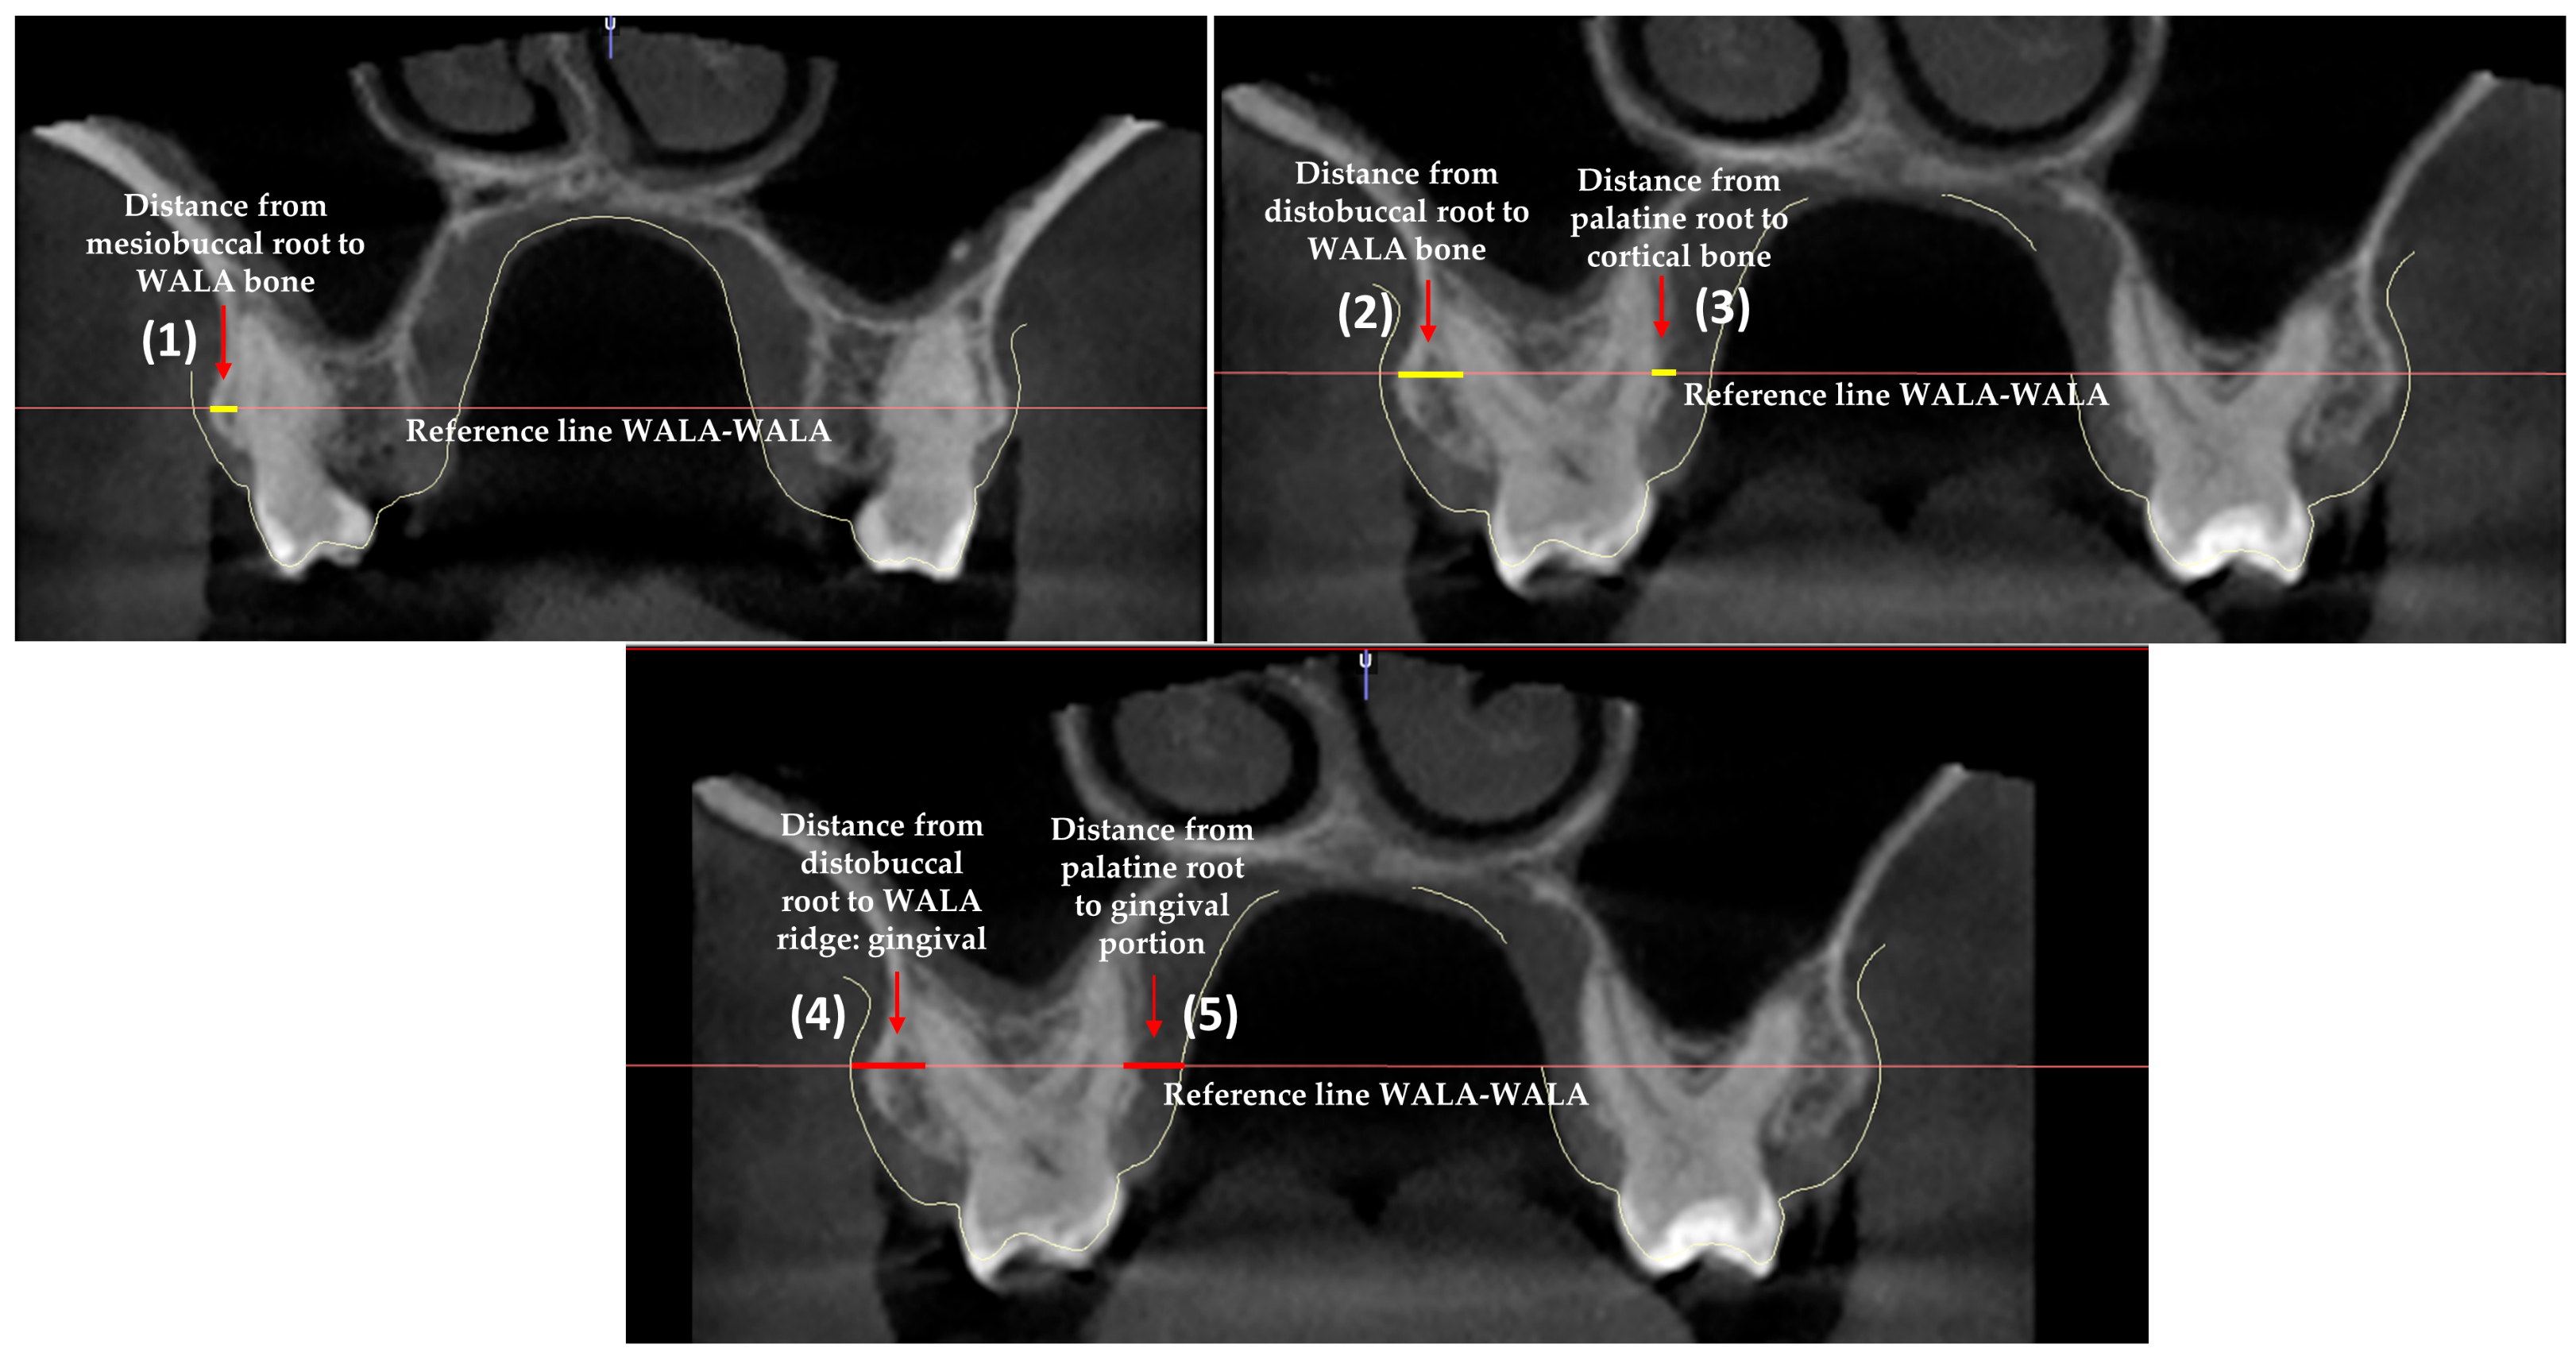

2. Materials and Methods